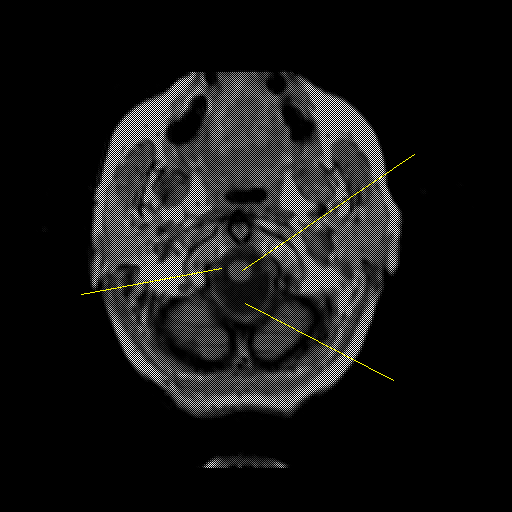

overlay: Slice 4

Slice 4

MRCBFCBF with

Unlabeled

Pointers

Labeled